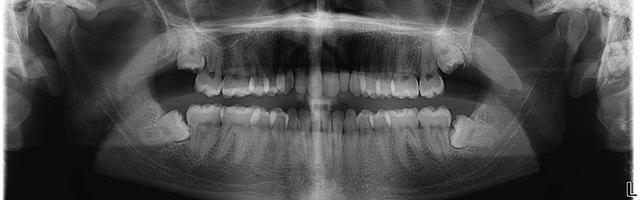

Le malattie parodontali sono sia quelle riguardanti le infiammazioni gengivali piu’ semplici, sia quelle piú gravi che danneggiano il tessuto morbido della gengiva e l’osso che sostiene i denti, e nei casi piú complicati si verifica la perdita dei denti.